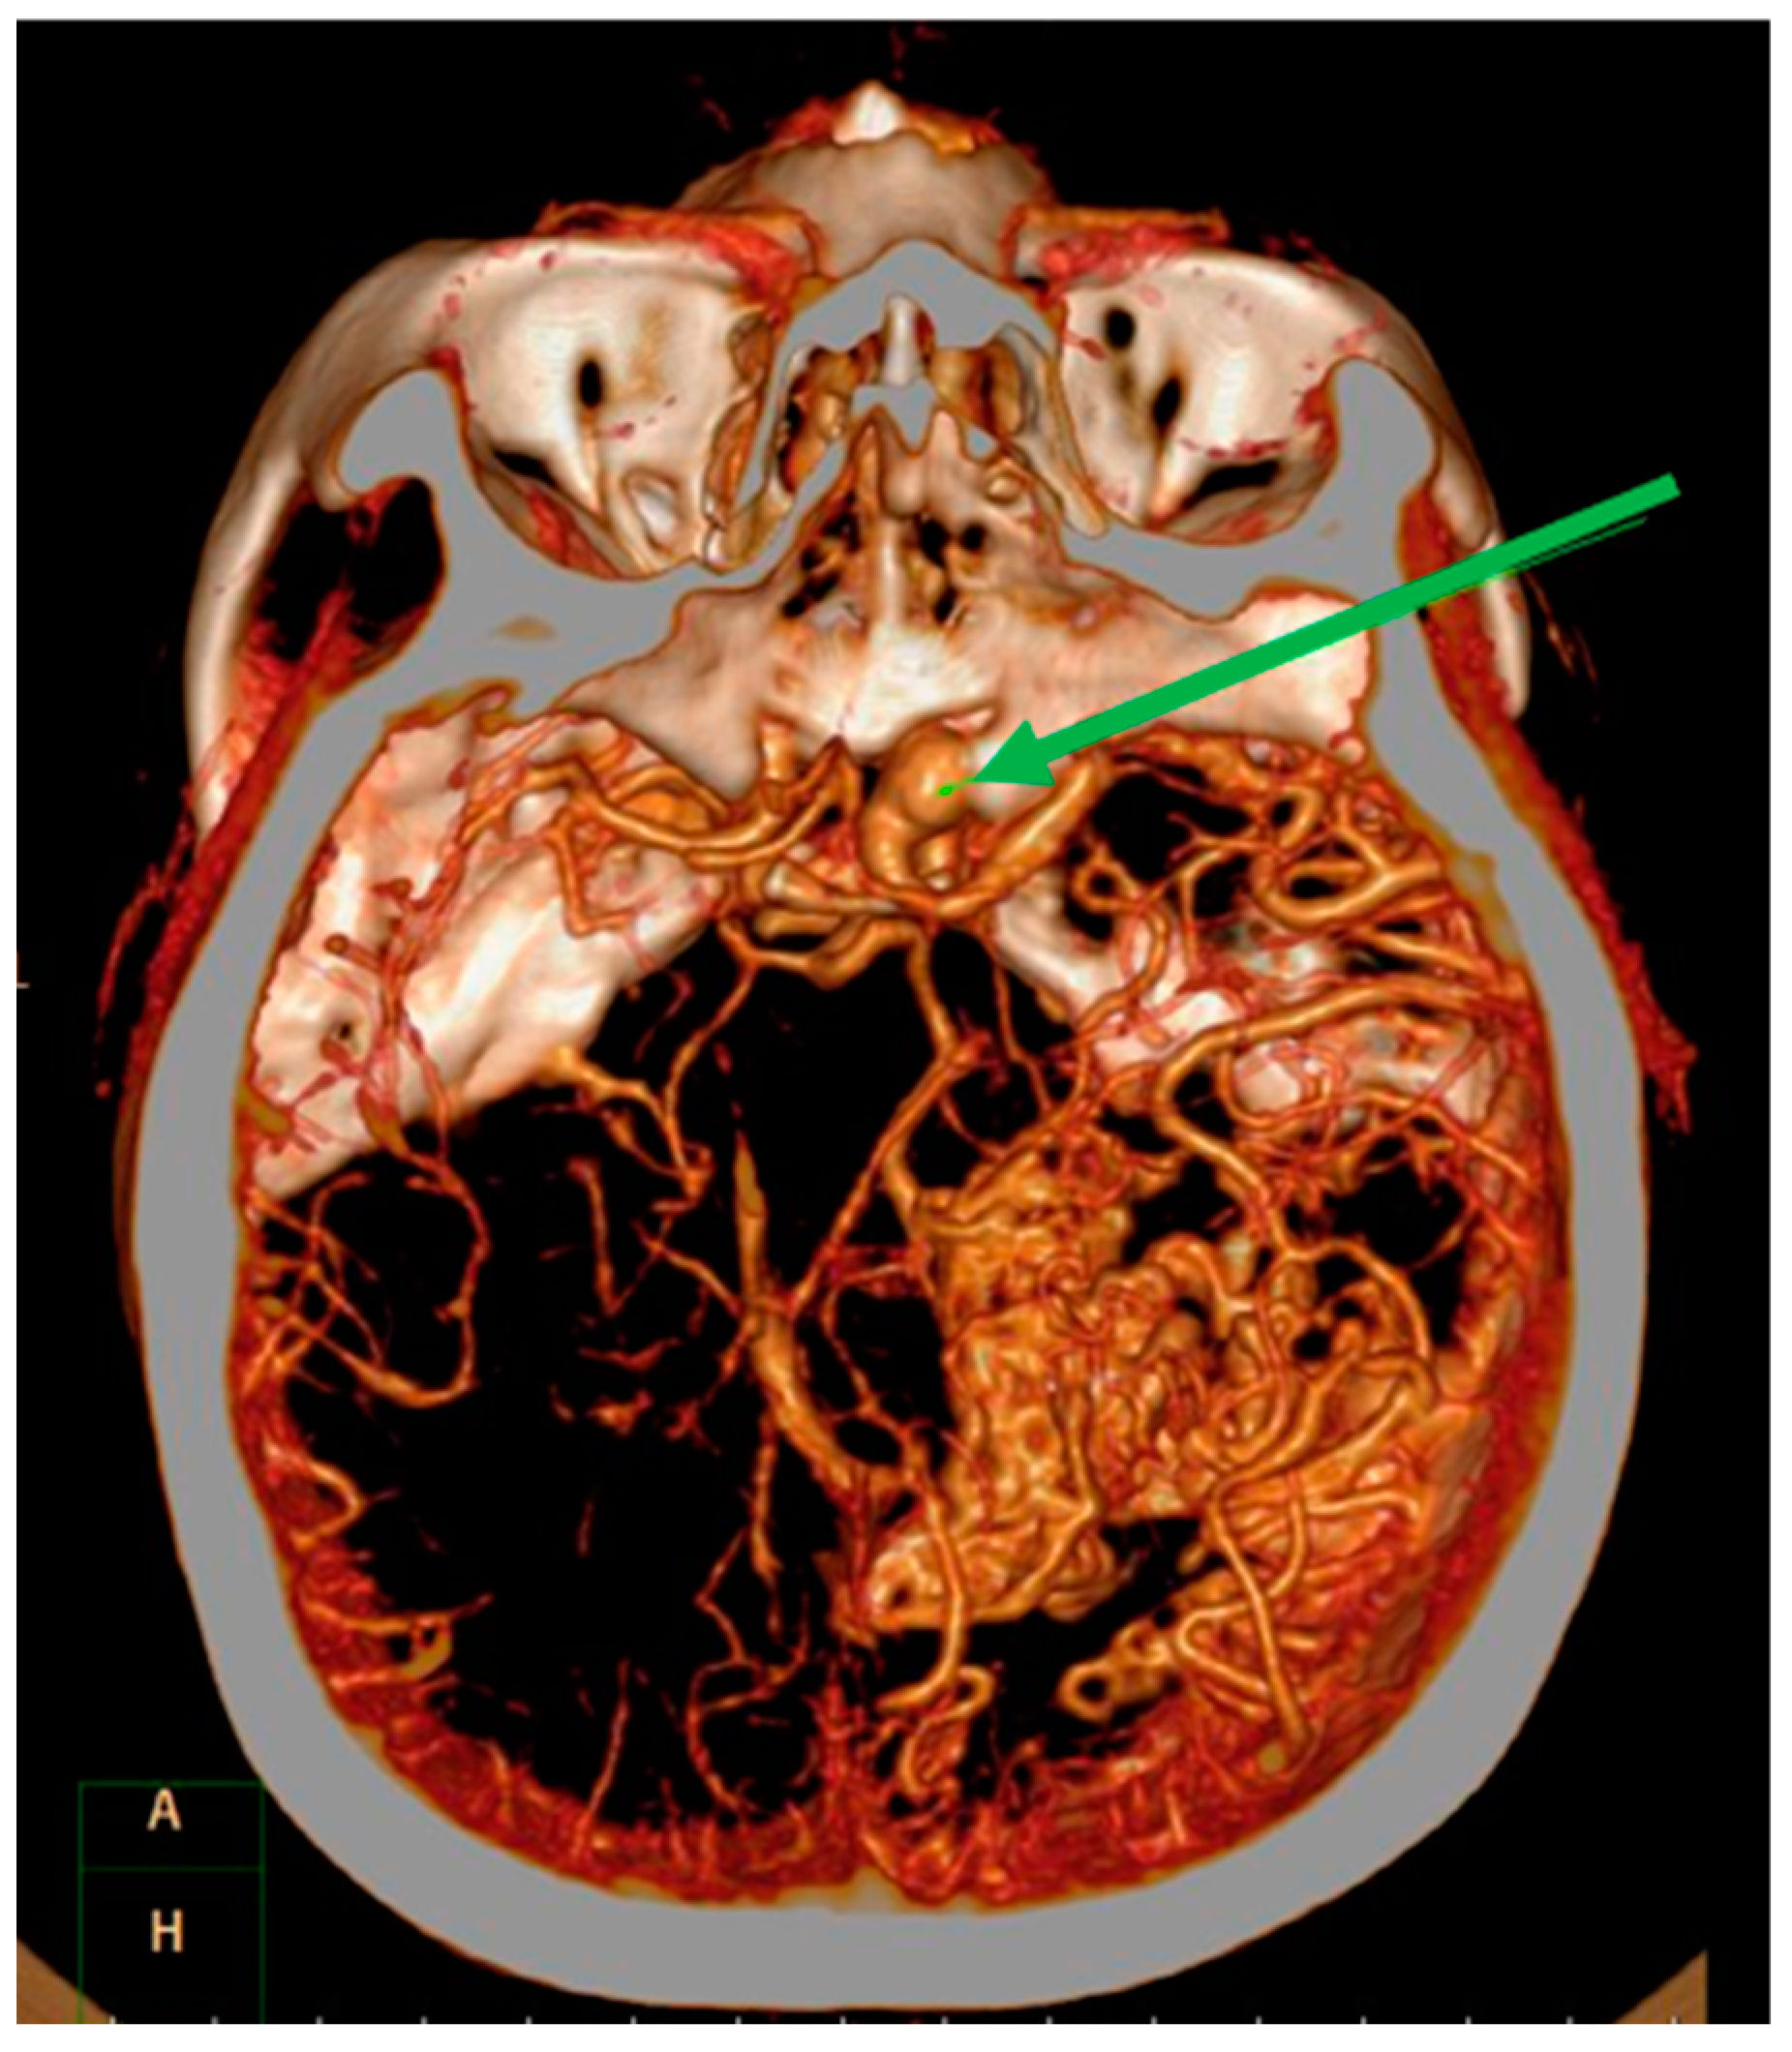

Magnetic resonance imaging (MRI) demonstrated a well enhanced mass, 1.1 cm × 2.3 cm in size, with a peri-focal edema in the right temporal lobe Figure 2A. In addition, surrounding and tangled dilated vessels in the right temporo-occipital area were noted on T1-weighted with gadolinium Figure 2B. Computed tomographic angiography (CTA) also confirmed these lesions Figure 3. Upon additional CTA study, the presence of arteriovenous malformation (AVM) nidus at the right temporal-parietal occipital region with arterial feeding from the right middle cerebral artery (MCA) and posterior cerebral artery (PCA), which then drained to the right transverse-sigmoid sinus via an engorged drainage vein, was noted.

Figure 3.

Computed tomography angiography. Imaging revealed focal heterogeneous enhancement with a surrounding multilinear contrast structure, and a lower density and calcified spots in the right temporal-parietal occipital lobe. The green arrow shows an ipsilateral supraclinoid internal carotid artery aneurysm.